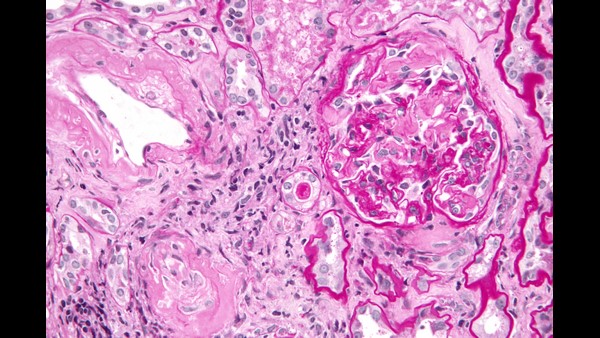

ಸಾಮಾನ್ಯವಾಗಿ ಈ ಅಮಿಲೋಯ್ಡೋಸಿಸ್ ಎನ್ನುವುದು ದೇಹದಾದ್ಯಂತ ಅಂಗಗಳು ಮತ್ತು ಅಂಗಾಂಶಗಳಲ್ಲಿ ಅಮಿಲಾಯ್ಡ್ ಎಂಬ ಅಸಹಜ ಪ್ರೋಟೀನ್ನ ರಚನೆಯಿಂದ ಉಂಟಾಗುವ ಅಪರೂಪದ, ಗಂಭೀರ ಪರಿಸ್ಥಿತಿಗಳನ್ನು ಸೃಷ್ಟಿಸುವ ಗುಂಪಿನ ಹೆಸರಾಗಿದೆ. ಅಮಿಲಾಯ್ಡ್ ಮೂಳೆ ಮಜ್ಜೆಯಲ್ಲಿ ಉತ್ಪತ್ತಿಯಾಗುವ ಅಸಹಜ ಪ್ರೋಟೀನ್ ಆಗಿದೆ. ಯಾವುದೇ ಅಂಗಾಂಶ ಅಥವಾ ಅಂಗದಲ್ಲಿ ಇದು ಹುಟ್ಟಿಕೊಳ್ಳಬಹುದು. ಅಮಿಲಾಯ್ಡ್ ಪ್ರೋಟೀನ್ಗಳ ರಚನೆಯಿಂದಾಗಿ ದೇಹದಲ್ಲಿ ಅಂಗಗಳು ಮತ್ತು ಅಂಗಾಂಶಗಳು ಸರಿಯಾಗಿ ಕೆಲಸ ಮಾಡುವುದಕ್ಕೆ ಕಷ್ಟವಾಗತ್ತದೆ. ಯುಕೆಯ ರಾಷ್ಟ್ರೀಯ ಆರೋಗ್ಯ ಸೇವೆ ಪ್ರಕಾರ, ಇದು ಅಂಗಾಂಗ ವೈಫಲ್ಯಕ್ಕೆ ಕಾರಣವಾಗುತ್ತದೆ.

ಅಮಿಲಾಯ್ಡೋಸಿಸ್ನ ಹೆಚ್ಚಿನ ಜನರು ತಮ್ಮ ಮೂತ್ರಪಿಂಡಗಳಲ್ಲಿ ಅಮಿಲಾಯ್ಡ್ ಪ್ರೋಟೀನ್ಗಳ ಸಂಗ್ರಹವನ್ನು ಹೊಂದಿರುತ್ತಾರ. ಇದರಿಂದ ಮೂತ್ರಪಿಂಡ ವೈಫಲ್ಯದ ಅಪಾಯವನ್ನು ಎದುರಿಸುತ್ತಾರೆ. ಈ ಸಮಸ್ಯೆಯ ಜೊತೆಗೆ ಹಲವು ಆರೋಗ್ಯ ಸಮಸ್ಯೆಗಳನ್ನು ಸೂಚಿಸುವ ಲಕ್ಷಣಗಳು ರೋಗಿಗಳಲ್ಲಿ ಗೋಚರಿಸುತ್ತವೆ. ಅವುಗಳೆಂದರೆ,

ಎಎಲ್ ಅಮಿಲೋಯ್ಡೋಸಿಸ್ ಮೂಳೆ ಮಜ್ಜೆಯಲ್ಲಿ ಕಂಡುಬರುವ ಕೆಲವು ಜೀವಕೋಶಗಳಲ್ಲಿನ ಅಸಹಜತೆಯಿಂದ ಉಂಟಾಗುತ್ತದೆ. ಇದನ್ನು ಪ್ಲಾಸ್ಮಾ ಜೀವಕೋಶಗಳು ಎಂದು ಕರೆಯಲಾಗುತ್ತದೆ. ಅಸಹಜ ಪ್ಲಾಸ್ಮಾ ಕೋಶಗಳು ಬೆಳಕಿನ ಸರಪಳಿ ಪ್ರೋಟೀನ್ಗಳ ಅಸಹಜ ರೂಪಗಳನ್ನು ಉತ್ಪಾದಿಸುತ್ತವೆ, ಇದು ರಕ್ತಪ್ರವಾಹಕ್ಕೆ ಪ್ರವೇಶಿಸುತ್ತದೆ ಮತ್ತು ಅಮಿಲಾಯ್ಡ್ ಅನ್ನು ರೂಪಿಸುತ್ತದೆ. ಈ ಆರೋಗ್ಯವಂತ ಜನರು ತಮ್ಮ ರಕ್ತದಲ್ಲಿ ಸಾಮಾನ್ಯ ಬೆಳಕಿನ ಸರಪಳಿ ಪ್ರೋಟೀನ್ಗಳನ್ನು ಹೊಂದಿರುತ್ತಾರೆ, ಅದು ಅವರ ನೈಸರ್ಗಿಕ ಪ್ರತಿಕಾಯ ಪ್ರೋಟೀನ್ಗಳ ಭಾಗವಾಗಿರುತ್ತದೆ. ಇವು ದೇಹವನ್ನು ಸೋಂಕಿನಿಂದ ರಕ್ಷಿಸಲು ಸಹಾಯ ಮಾಡುತ್ತವೆ.

AL ಅಮಿಲೋಯ್ಡೋಸಿಸ್ ರೋಗಿಗಳಲ್ಲಿನ ಅಸಹಜ ಬೆಳಕಿನ ಸರಪಳಿಗಳು ಥ್ರೆಡ್ ತರಹದ ರೀತಿಯಲ್ಲಿ (ಅಮಿಲಾಯ್ಡ್ ಫೈಬ್ರಿಲ್ಗಳು) ಒಟ್ಟಿಗೆ ಸೇರಿಕೊಳ್ಳುತ್ತವೆ, ಅದನ್ನು ದೇಹದಿಂದ ಸುಲಭವಾಗಿ ತೆರವುಗೊಳಿಸಲು ಸಾಧ್ಯವಾಗುವುದಿಲ್ಲ. ಕಾಲಾನಂತರದಲ್ಲಿ, ಅಮಿಲಾಯ್ಡ್ ಫೈಬ್ರಿಲ್ಗಳು ಅಂಗಾಂಶಗಳು ಮತ್ತು ಅಂಗಗಳಲ್ಲಿ AL ಅಮಿಲಾಯ್ಡ್ ಅನ್ನು ನಿರ್ಮಿಸುತ್ತವೆ. ಕ್ರಮೇಣ ಇದು ಸರಿಯಾಗಿ ಕಾರ್ಯನಿರ್ವಹಿಸುವುದನ್ನು ನಿಲ್ಲಿಸುತ್ತದೆ, ಹೀಗಾಗಿ AL ಅಮಿಲೋಯ್ಡೋಸಿಸ್ ಹಲವು ರೋಗಲಕ್ಷಣಗಳನ್ನು ಉಂಟುಮಾಡುತ್ತದೆ. ಇತರ ಕೆಲವು ವಿಧದ ಅಮಿಲೋಯ್ಡೋಸಿಸ್ ಗಿಂತ ಭಿನ್ನವಾಗಿ AL ಅಮಿಲೋಯ್ಡೋಸಿಸ್ ಆನುವಂಶಿಕವಾಗಿಲ್ಲ. ಆದ್ದರಿಂದ ಈ ಸ್ಥಿತಿಯನ್ನು ಹೊಂದಿರುವ ವ್ಯಕ್ತಿಯು ಅದನ್ನು ತಮ್ಮ ಮಕ್ಕಳಿಗೆ ರವಾನಿಸಲು ಸಾಧ್ಯವಿಲ್ಲ. ಅದೇ ರೀತಿ ಈ ರೋಗಾಣು ವ್ಯಕ್ತಿಯಿಂದ ವ್ಯಕ್ತಿಗೆ ಹರಡುವಂಥದ್ದೂ ಅಲ್ಲ ಎಂದು ತಜ್ಞರು ಹೇಳುತ್ತಾರೆ.